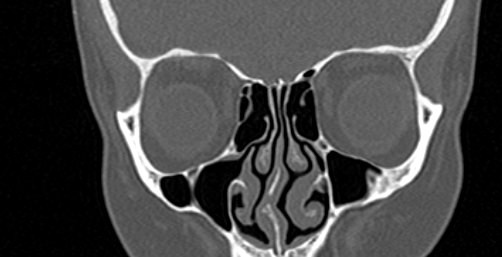

Орбиты (или глазницы) – это костные углубления в лицевом черепе, где расположены глазные яблоки, окруженные жировой клетчаткой, а также слезные железы, слезные каналы, сосуды, нервы, мышцы и связки глаза. Такая небольшая по объему область содержит важные анатомические структуры, обеспечивающие нормальную функцию органа зрения.

Кроме того, область орбиты тесно связана с близлежащими структурами – полостью черепа с расположенным в ней головным мозгом, а также с полостью носа, околоносовыми пазухами и носоглоткой. Различные патологические процессы могут развиваться как в самой глазнице, так и в околоорбитальных структурах, но при этом распространяться на область орбит.

Мультиспиральная компьютерная томография лучше всего визуализирует ткани с высокой плотностью, к которым, в частности, относится костная ткань. Это делает КТ незаменимой при диагностике травматических повреждений глазниц, а также для выявления инородных тел орбит.

По результатам КТ орбиты глаза врач может оценить состояние:

- костных стенок глазницы, верхней и нижней глазничных щелей;

КТ орбит позволяет выявить:

- инородные тела в глазницах;

- переломы стенок глазниц;